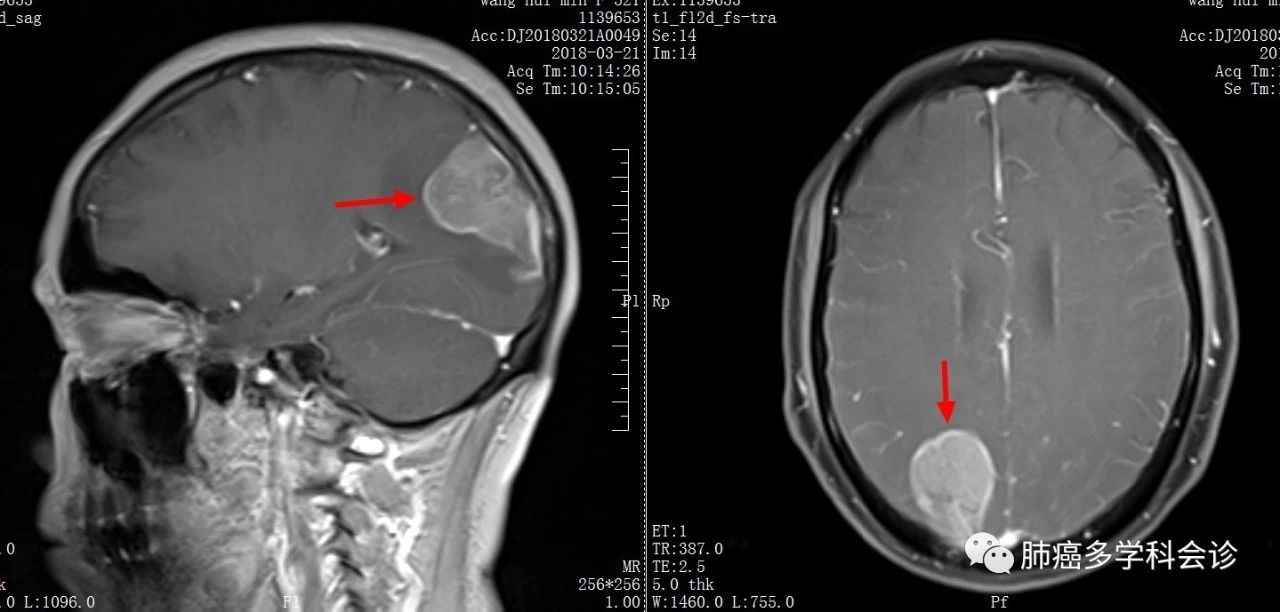

患者于2018年3月出现头痛,头颅核磁共振发现:右顶枕叶约 5cm的不均匀强化病灶,考虑脑转移。

脑巨大的单发转移灶,随行外科切除手术,术中见:肿瘤最大经约 6cm,呈囊实性变,囊内壁附着灰黄色物。

脑转移灶切除组织的病理:脑转移性腺癌,肺来源

基因检测:EGFR 21外显子 L858R突变